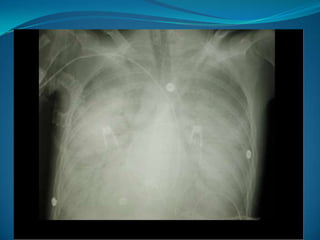

Douleurs péricardiques:  Dlde péricardite aigue: vive, antérieure, pseudoangineuse, modifiée par la respiration, atténuée par la position penchée en avant.  Contexte viral précessif ou associé avec fièvre.  Auscultation: frottement péricardique fugace.  ECG: pas de signes ischémie, micro voltage, sus décalageST diffus et concave.  Radio pul: élargissement de silhouette cardiaque.  En absence de dl+fièvre+frottement, une échocardio permet de confirmée le Dg.  Syndrome de Dressler: complication dans 1ére semaine post IDM(épanchement péricardique+fièvre).